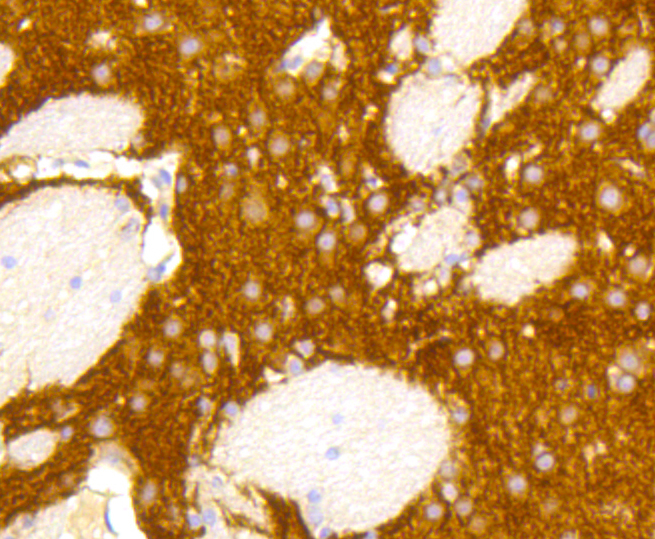

Immunohistochemistry of paraffin-embedded mouse brain using GRM5 antibody at dilution of 1:100 (40x lens).

Immunohistochemistry of paraffin-embedded rat brain using GRM5 antibody at dilution of 1:100 (40x lens).